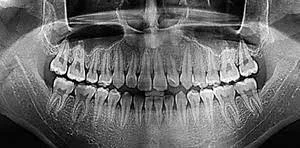

А у меня Рентенологическая служба. :bounce:. Могу Фиксажа на серебро накапать.;)